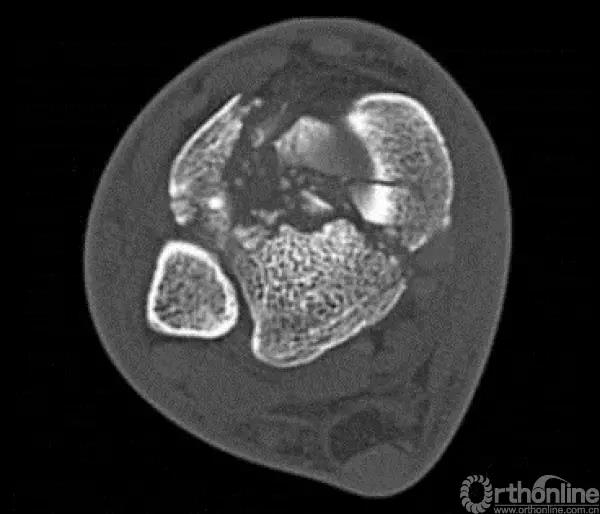

Pilon骨折为发生于胫骨远端并累及关节面,由垂直暴力合并或不合并扭转暴力导致的骨折,常表现为干骺端的压缩和关节面的粉碎。它是踝部的复杂骨折,以高能量损伤、不稳定、软组织损伤严重为特点。

2.中心粉碎骨折

对于中心粉碎骨折需要充分牵引、撑开,将关节面的骨折块先找到摆放在合适的位置,用克氏针将关节面的骨块应用排筏技术先固定好,从下方观察关节面的复位情况,并且确认骨块不会向上推起,适当植骨,然后将骨块前后和左右进行压实后进行固定。